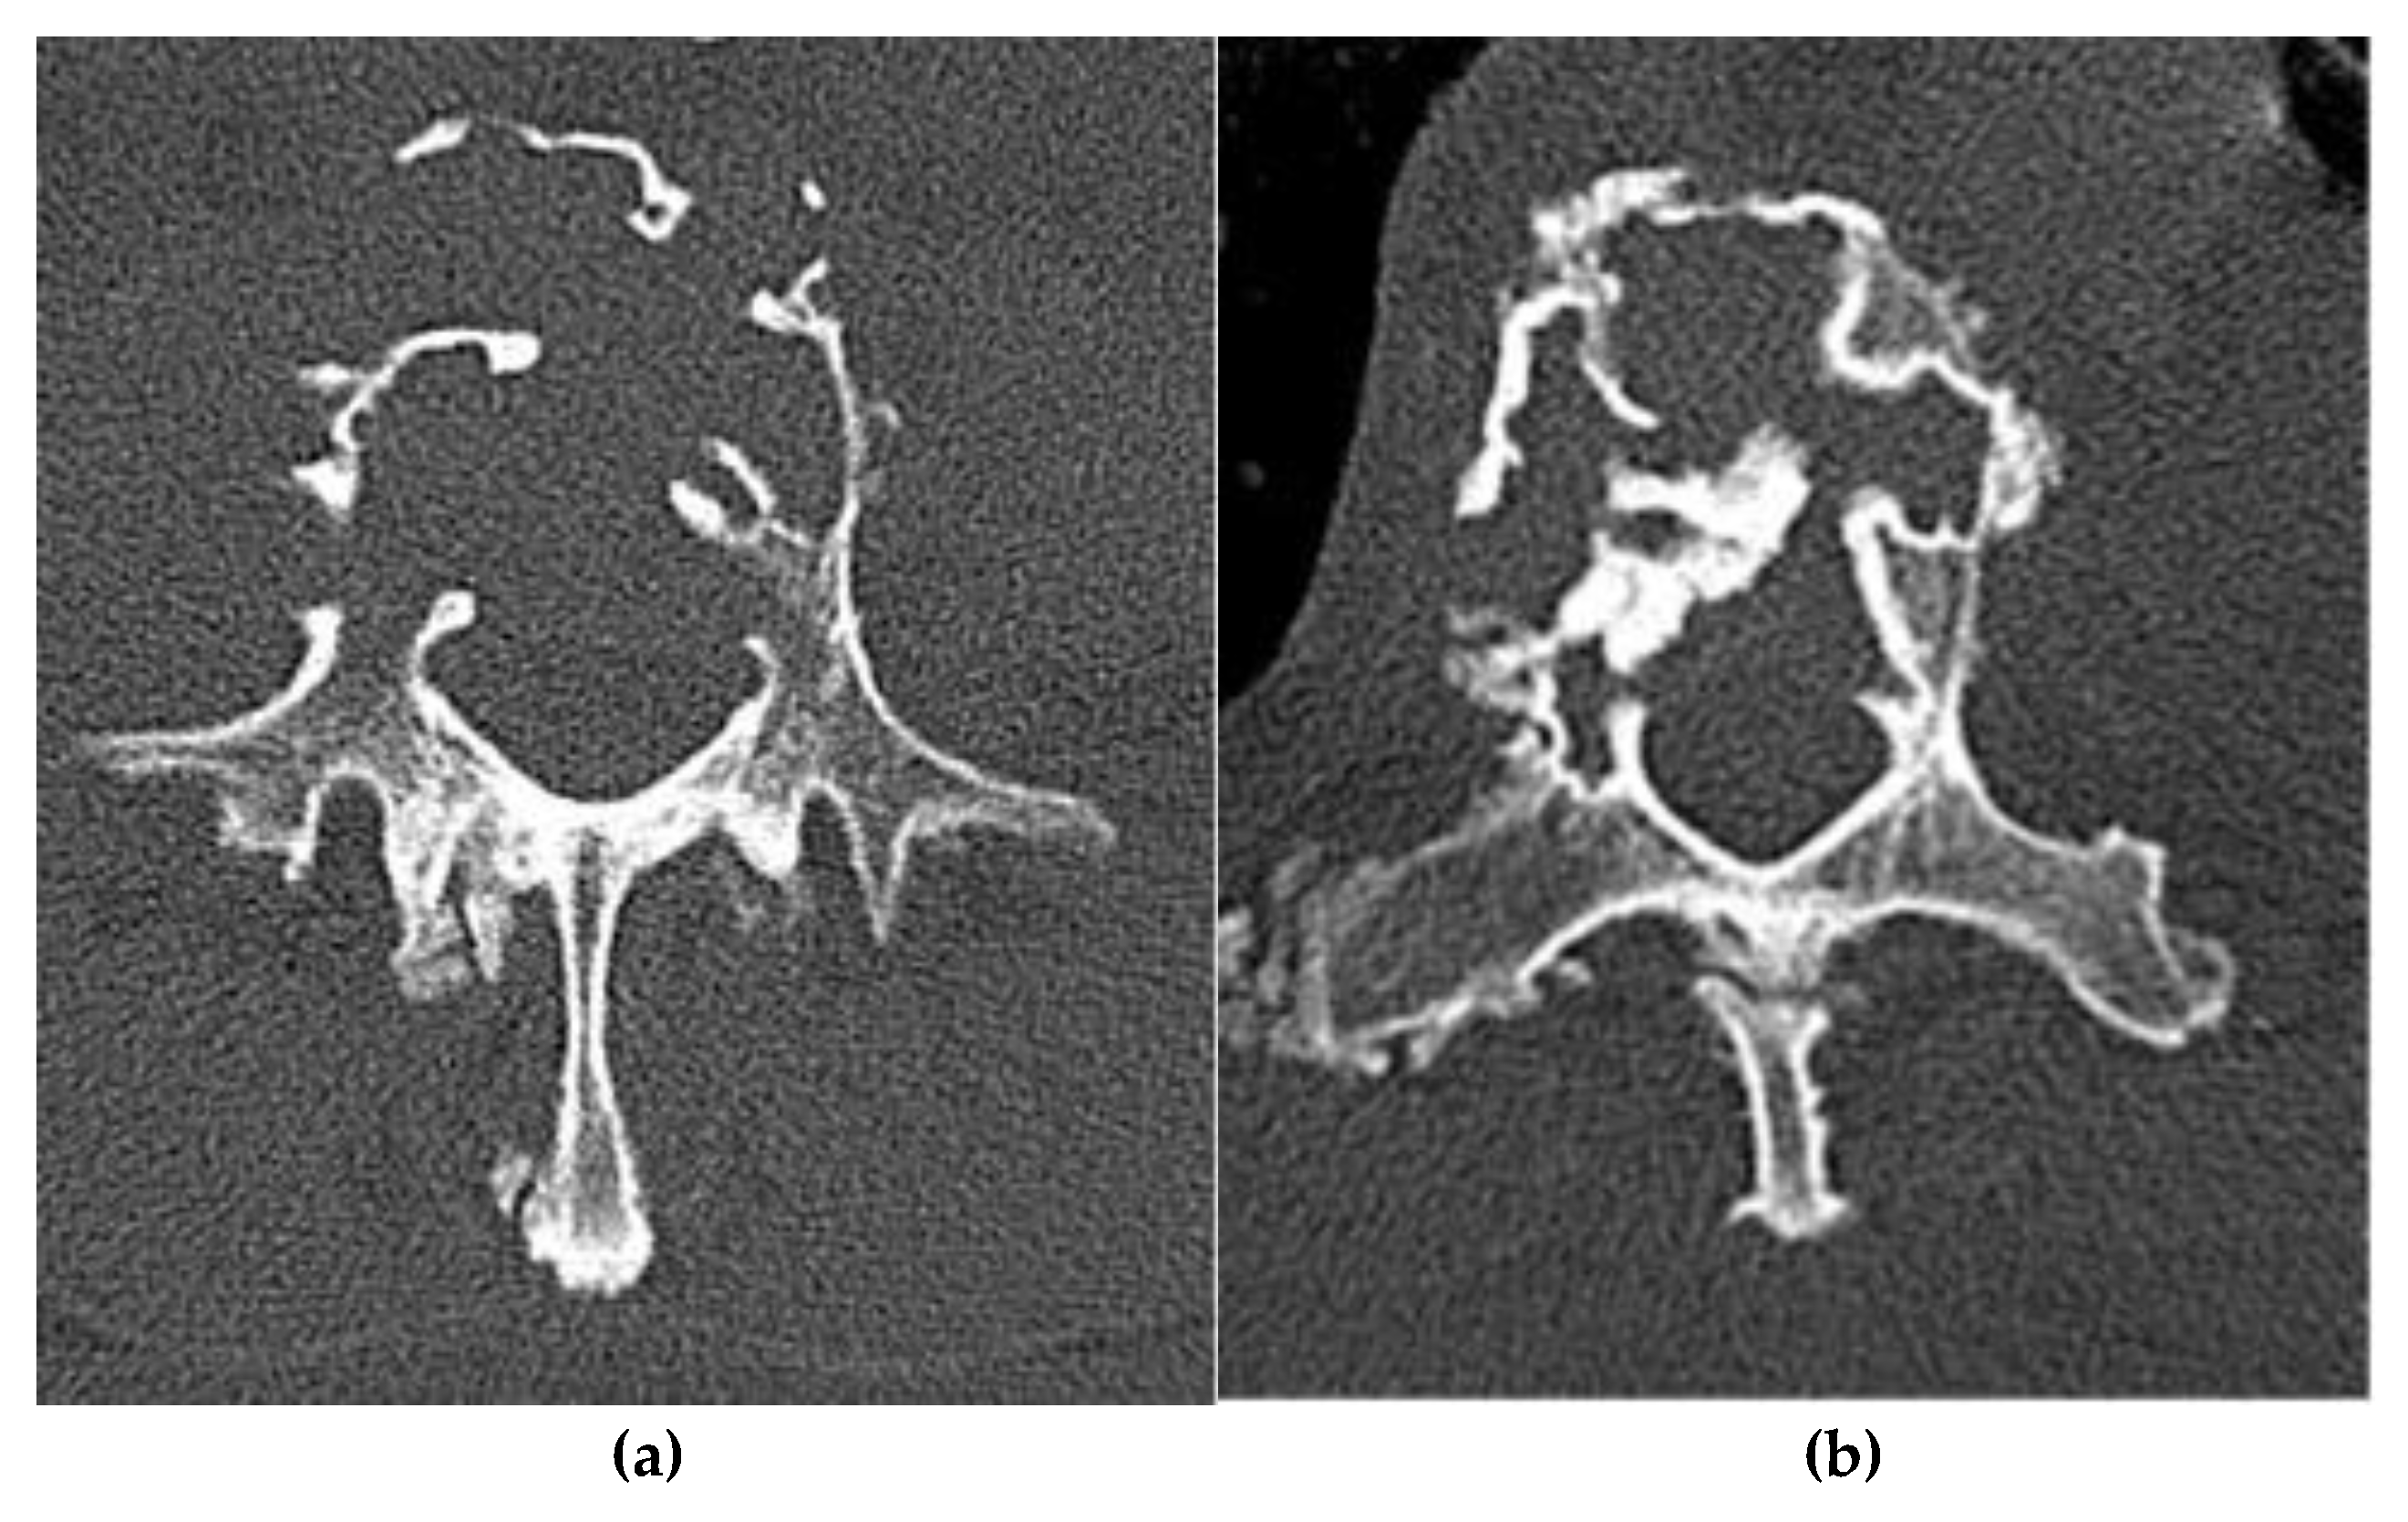

Osteochondroma

Chondroblastoma

- Sinelnikov, A. , & Kale, H. Osteochondromas of the Spine. Clin. Radiol. 2014, 69, e584–e590. [Google Scholar] [CrossRef]

- Rajakulasingam, R. , Murphy, J., Botchu, R., & James, S. L. Osteochondromas of the Cervical Spine: Case Series and Review. J. Clin. Orthop. Trauma 2020, 11, 905–909. [Google Scholar] [CrossRef]

- Patnaik, S. , Jyotsnarani, Y., Uppin, S. G., & Susarla, R. Imaging Features of Primary Bone Tumors of the Spine: A Pictorial Essay. Indian J. Radiol. Imaging 2016, 26, 279–289. [Google Scholar] [CrossRef]

- Yakkanti, R. , Onyekwelu, I., Carreon, L. Y., & Dimar, J. R. Solitary Osteochondroma of the Spine - A Case Series: Review of Solitary Osteochondroma With Myelopathic Symptoms. Global Spine J. 2018, 8, 323–339. [Google Scholar] [CrossRef]